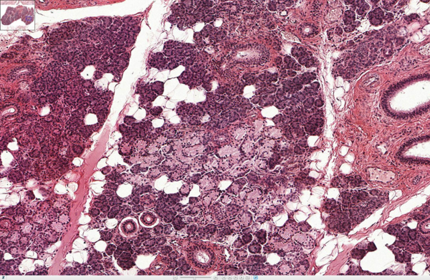

parotid gland lots of fat cells

how can you tell this is the parotid gland? it only does serous secretion and you can see fat